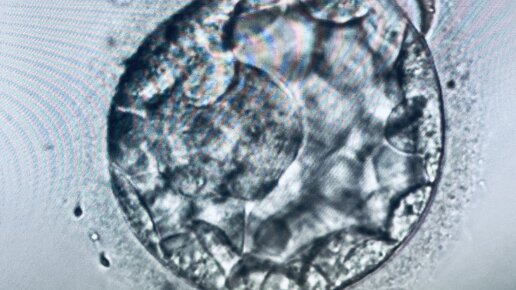

Поговорим об эмбрионах 5-6 суток развития - стадии бластоцисты. Эмбрион состоит из 2 слоев: в зависимости от размера эмбриона на стадии бластоцисты проводят оценку качества эмбрионов по внешним морфологическим критериям ❓Что означают ЦИФРЫ Цифры свидетельствуют о количестве клеток эмбриона на данном этапе развития: 1️⃣ – это появление ранней бластоцисты 2️⃣ - полость бластоцисты больше, чем половина эмбриона  («средняя» бластоциста) 3️⃣ – растущая бластоциста, полость заполняет почти весь эмбрион 4️⃣ - развитая бластоциста, тонкая наружная оболочка 5️⃣ - бластоциста «вылупляется», т...

Селекция бластоцист на основании 3 суток развития

Исследовательский вопрос: возможно ли выбрать оптимальный эмбрион на перенос, основываясь на морфологии эмбриона на третьи сутки. Отбор "качественного" эмбриона - один из ключевых факторов успешной программы ЭКО. Морфология эмбриона служит одним из критериев оценки его потенциала. Оценка качества бластоцисты основывается на системе классификации Гарднера (стадия роста, классификация внутренней клеточной массы и трофэктодермы). При выборе эмбриона на перенос предпочтение отдается бластоцистам 5 суток с более высокими морфологическими показателями...